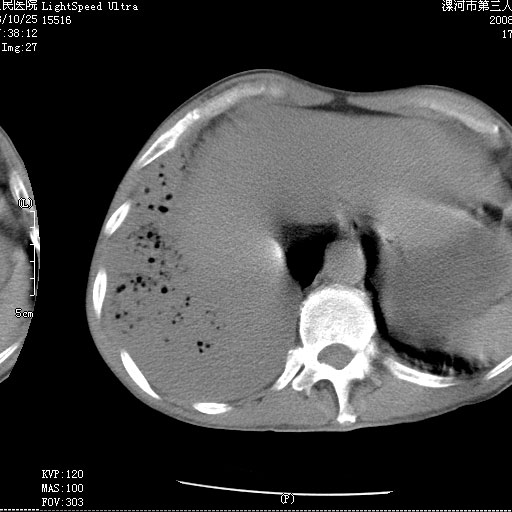

m 老年 发烧、呼吸困难,慢支、肺气肿多年;记的那次是下午大概17:38做的,晚上窒息死亡。

上面的层面就慢性支气管炎肺气肿、肺大泡,别的没有什么、也就不传了。

当时我怀疑:1、阻塞性肺不张早期 2、肺脓肿早期,望老师们发表意见

应该是脓胸的表现,右下肺气管阻塞考虑为痰栓.

你怀疑的有道理,慢支、肺气肿、肺打泡是有了,右下肺的病变有待商议;

首先考虑右下肺炎症并不张,不除外早期肺泡癌改变

病灶边缘清---多个含气小腔---近端未见通畅气管影-----支持-----慢性肺脓肿继发阻塞性肺不张

阻塞性肺不张原因-----脓液未排出

1、右侧脓胸;2、copd;

3、细支气管肺泡癌可以排除,病变以斜裂为界,呈大片状高密度影,内可见多发小气泡,表明有产气杆菌感染所致,内无明显的支气管“枯树枝征”表现,再结合其临床改变(细支气管肺泡癌临表表现重、影像表现轻)所以不符合细支气管肺泡癌(炎症型)的改变。

考虑为右肺下叶支气管痰栓形成并阻塞性肺不张及肺炎。

病变按肺叶分布,病变内可见多个小空腔影,未见充气支气管影,中间段支气管管腔肺窗示密度欠均匀,下肺支气管分叉处基底段支气管隐约可见,未见明显狭窄,中叶支气管通畅,

考虑:阻塞性肺炎伴小脓肿形成可能性大。(痰栓可能性大)

右下肺实变,内有弥漫分面小气泡而无支气管征,叶间裂前移,呈臌大之形,而无收缩之状,兼纵隔稍左行移,故。不支持不张,倒支持大叶肺叶,如楼上所说,小气泡不象残留之肺,不可以考虑产气菌感染吗。

阻塞性肺炎,肺脓肿形成。依据,右下支气管不通,大片实变形内可见小气泡。不支持肺不张。